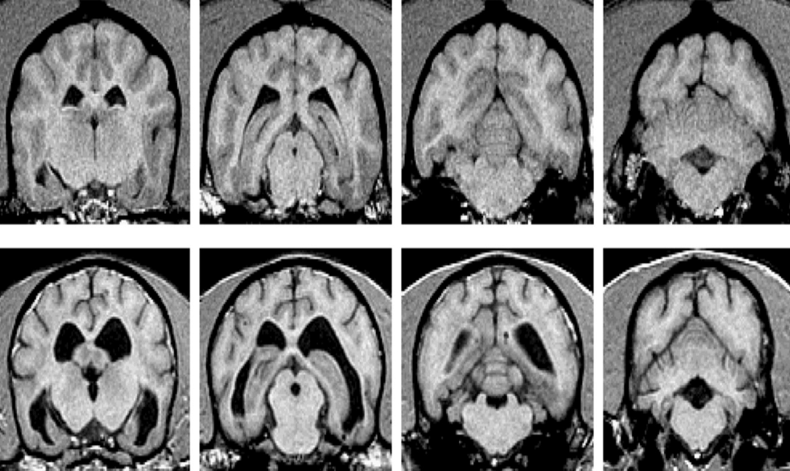

์ ์ ๊ฐ์ ๋ vs. ๋์ด๋ ๊ฐ์ ๋

15์ด ๋(์๋) : sulcus, gyrus๊ฐ ๋ ํ์ฅ. lateral ventricle์ด ํฌ๊ณ , cortex atrophy๊ฐ ํจ์ฌ ์ฌํจ.